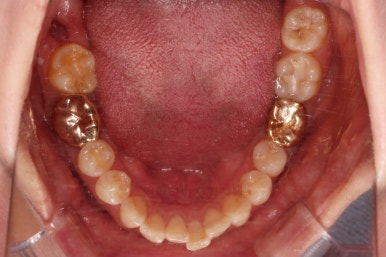

마찬가지로 부산치아교정비용 초진 시 입안의 모습입니다.

아랫니가 많이 보이지 않는 타입이라서 잘 몰랐는데 입안을 관찰해 보니 아래 앞니가 삐뚤어 있네요.

이 부분도 꼭 교정해야 될 정도는 아니여서 선택의 문제라고 할 수 있는데요.

어금니가 문제였습니다.

윗니 어금니가 하나 없는 상태였고요.

어금니가 없이 지낸지 꽤 시간이 흐른터라 뒤쪽 어금니가 앞으로 쓰러져 공간을 잠식하고 있었습니다.